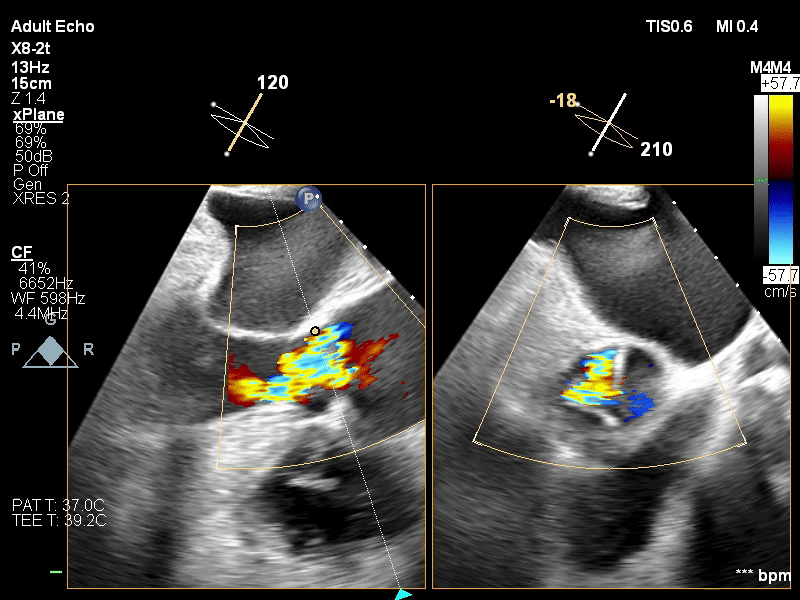

瓣膜释放前经食道超声

瓣膜释放后食道超声